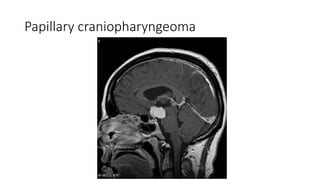

• Papillary Craniopharyngeoma

Papillary craniopharyngeoma

Differential diagnosis • PapillaryCraniopharyngeoma • Chaismatic-hypothalamic glioma

Differtiating points Suprasellarmeninigioma Papillary Craniophayngioma Chaismatic Hypothalamic glioma Definition A tumour originating from arachnoid cell rest(which are related to dura mater arachnoid granulations) A benign mostly solid suprasellar tumor arising from squamous epithelial remnants of rathke’s pouch An astrocytic tumor Age Middle decades Middle decades Usually 4rth to 6th decade Childhood Location and extention Tebercular , dorsal or diapgragm sellae Often shows forward extension along dura mater of anterior cranial fossa Commonly located within the suprasellar region A purely intrasellar location is uncommon optic chiasm and optic tract. Chaismal tumor tumors may into hypothalamus

Differentiatig points Suprasellarmeningioma Papiilary Craniopharyngioma Chiasmatic Hypothamic glioma NECT Usullally broad dural based, hyperdense lesion Calcification is seen 20% cases Usuully solid suprasellar tumour Small cysts but not a significant feature calcification is absent Often large and lobulated when at chiasm and can extend into hypothalamus No calcification CECT/MRC+ Avidly homogenous enhancement Soild component-intense contrast inhencement Variable inhancement T2WI Frequently isointense to cortex High signal intesity High signal intensity Bony hyperostosis Usually present Absent Absent Dural tail sign Usually present Absent Absent